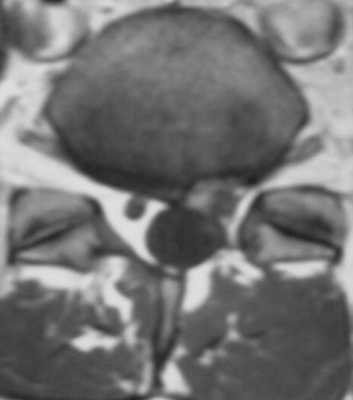

Фораминальная рецидивная грыжа 5 мм. Дискография.

Сдавление корешка L4 в корешковом канале, несмотря на малые размеры грыжи. Эпидурография.